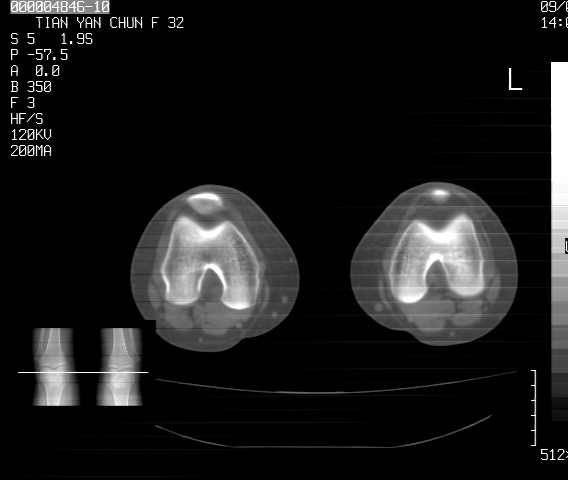

标题: CT18487:请会诊,女32岁,左膝疼痛数日 [打印本页]

标题: CT18487:请会诊,女32岁,左膝疼痛数日

关节面软骨有硬化环考虑退行性变

定位片可见髁间棘骨质增生,支持膝关节退行性变。

定位片可见髁间棘骨质增生,支持膝关节退行性变。建议mri 检查

考虑骨性关节炎